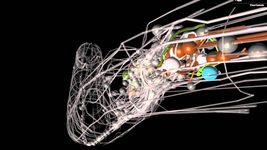

Neuralink шукає пацієнтів із паралічем по всьому світу для участі в дослідженнях мозкового чипа

Neuralink шукає пацієнтів із паралічем по всьому світу для участі в дослідженнях мозкового чипа

Жінка, яка не розмовляла 18 років після інсульту, знову заговорила завдяки мозково-комп'ютерному імплантату

Жінка, яка не розмовляла 18 років після інсульту, знову заговорила завдяки мозково-комп'ютерному імплантату

Паралізований чоловік, який мріяв літати, зміг керувати віртуальним дроном завдяки мозковому чипу Blackrock Neurotech зі штучним інтелектом

Паралізований чоловік, який мріяв літати, зміг керувати віртуальним дроном завдяки мозковому чипу Blackrock Neurotech зі штучним інтелектом